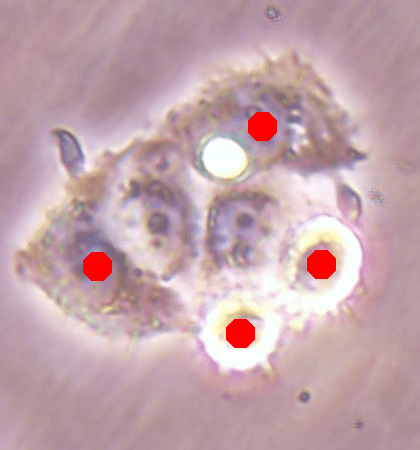

![]() |

| (a) | (b) |

| (c) | (d) |

For an example subimage given in Fig. 2a, these distance definitions are illustrated in Figs. 2b and 2c, respectively. The inner distance definition well indicates the cell centers since it uses the Euclidean distances from pixels to their closest cell centers. However, as it uses the centers as the reference point, the distance decrease from a center to its boundaries is the same for all directions and for all cells. Thus, when it is used alone, this definition imposes a circular and one-sized shape on the cells, as also seen in Fig. 2b. On the contrary, since the normalized outer distance is calculated with a reference to a cell boundary, this decrease may differ from one direction to another as well as from one cell to another, depending on the shape and size of the cell. Thus, it better preserves the morphological characteristics of cells, as seen in Fig. 2c.

The proposed DeepDistance model considers cell detection as a multi-task regression problem that estimates two distance maps from the RGB image, one for formulating the main task of cell detection and the other as an auxiliary task with the motivation of more effectively learning the main task. The FCN architecture given in the previous section is designed to learn these two regression tasks at the same time. This section discusses how this model can be extended to cover more auxiliary tasks, concurrent learning of which may further increase the performance of the main task. For this purpose, this section implements an extended version of the DeepDistance model that comprises an additional task of cell pixel classification. This additional task aims to construct a classification map (as shown in Fig. 2d) from the shared features of the encoder path111To take overlapping cells apart, and hence to obtain an improved map, cell boundaries are widen and subtracted from the classification map. This improved map is also used in the comparison methods to make fair comparisons.. Note that here, instead of defining another regression problem as the additional task, we use a classification problem in order to demonstrate that the model can easily be extended to cover the auxiliary tasks related with regression as well as classification.